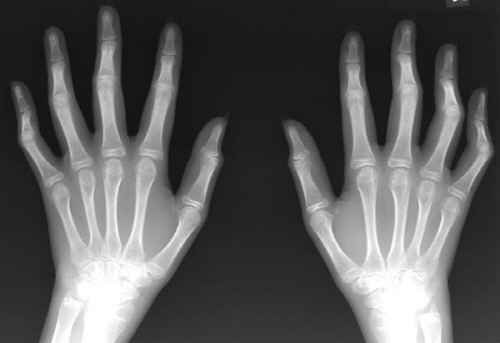

류머티즘 관절염은 신체 여러 부위에서 염증을 일으키는 만성 자가면역 질환이며 염증성 질환이다. 골관절염에 이어서 만성 관절염 중에서도 가장 흔한 원인의 질환이기도 하다. 류머티즘 관절염은 흔히 알고 있는 일반 관절염과는 다르다. 일반적으로 관절염이라고 하면 부상이나 노화 등으로 인해서 관절에 마모가 생기는 골관절염이다. 그리고 퇴행성 관절염은 일 할 때 손가락 마디가 붓고 아픈 증상이 심하다. 손가락 끝마디나 또는 중간 마디가 딱딱하게 돌출되었으면 퇴행성 관절염의 확률이 높다. 주로 50대 이상의 충장년층 여성에게서 많이 관찰되고 있다. 반복적인 수작업이나 노화로 인해서 연골이 닮아서 없어지고 대신에 뼈가 자라나는 현상이다. 반면에 류머티즘 관절염은 세균의 침투를 방어하다 면역계통에 이상이 생기는 것이다. 그래서 세포의 염증을 물질이 과다 분비되면서 신체 전신에 관절염을 일으키는 질환이다. 주로 손 관절에서 시작하지만 무릎이나 어깨와 발목 등 전신 관절에 나타나는 경우가 많다. 염증 물질이 가장 활발하게 움직이는 시간은 새벽 3시 정도 된다. 그래서 아침에 일어나면 경직감이나 뻣뻣한 증상이 발생하는 조조강직이 주요 증상으로 나타난다. 아침에 활동을 시작하면 증상은 서서히 완화되고 오후에는 호전이 되는 양상을 보인다. 류머티즘 관절염의 원인은 정확하게 밝혀져 있지는 않지만 유전적인 요인과 흡연 등 환경적인 요인이 영향을 주는 것으로 전해진다.